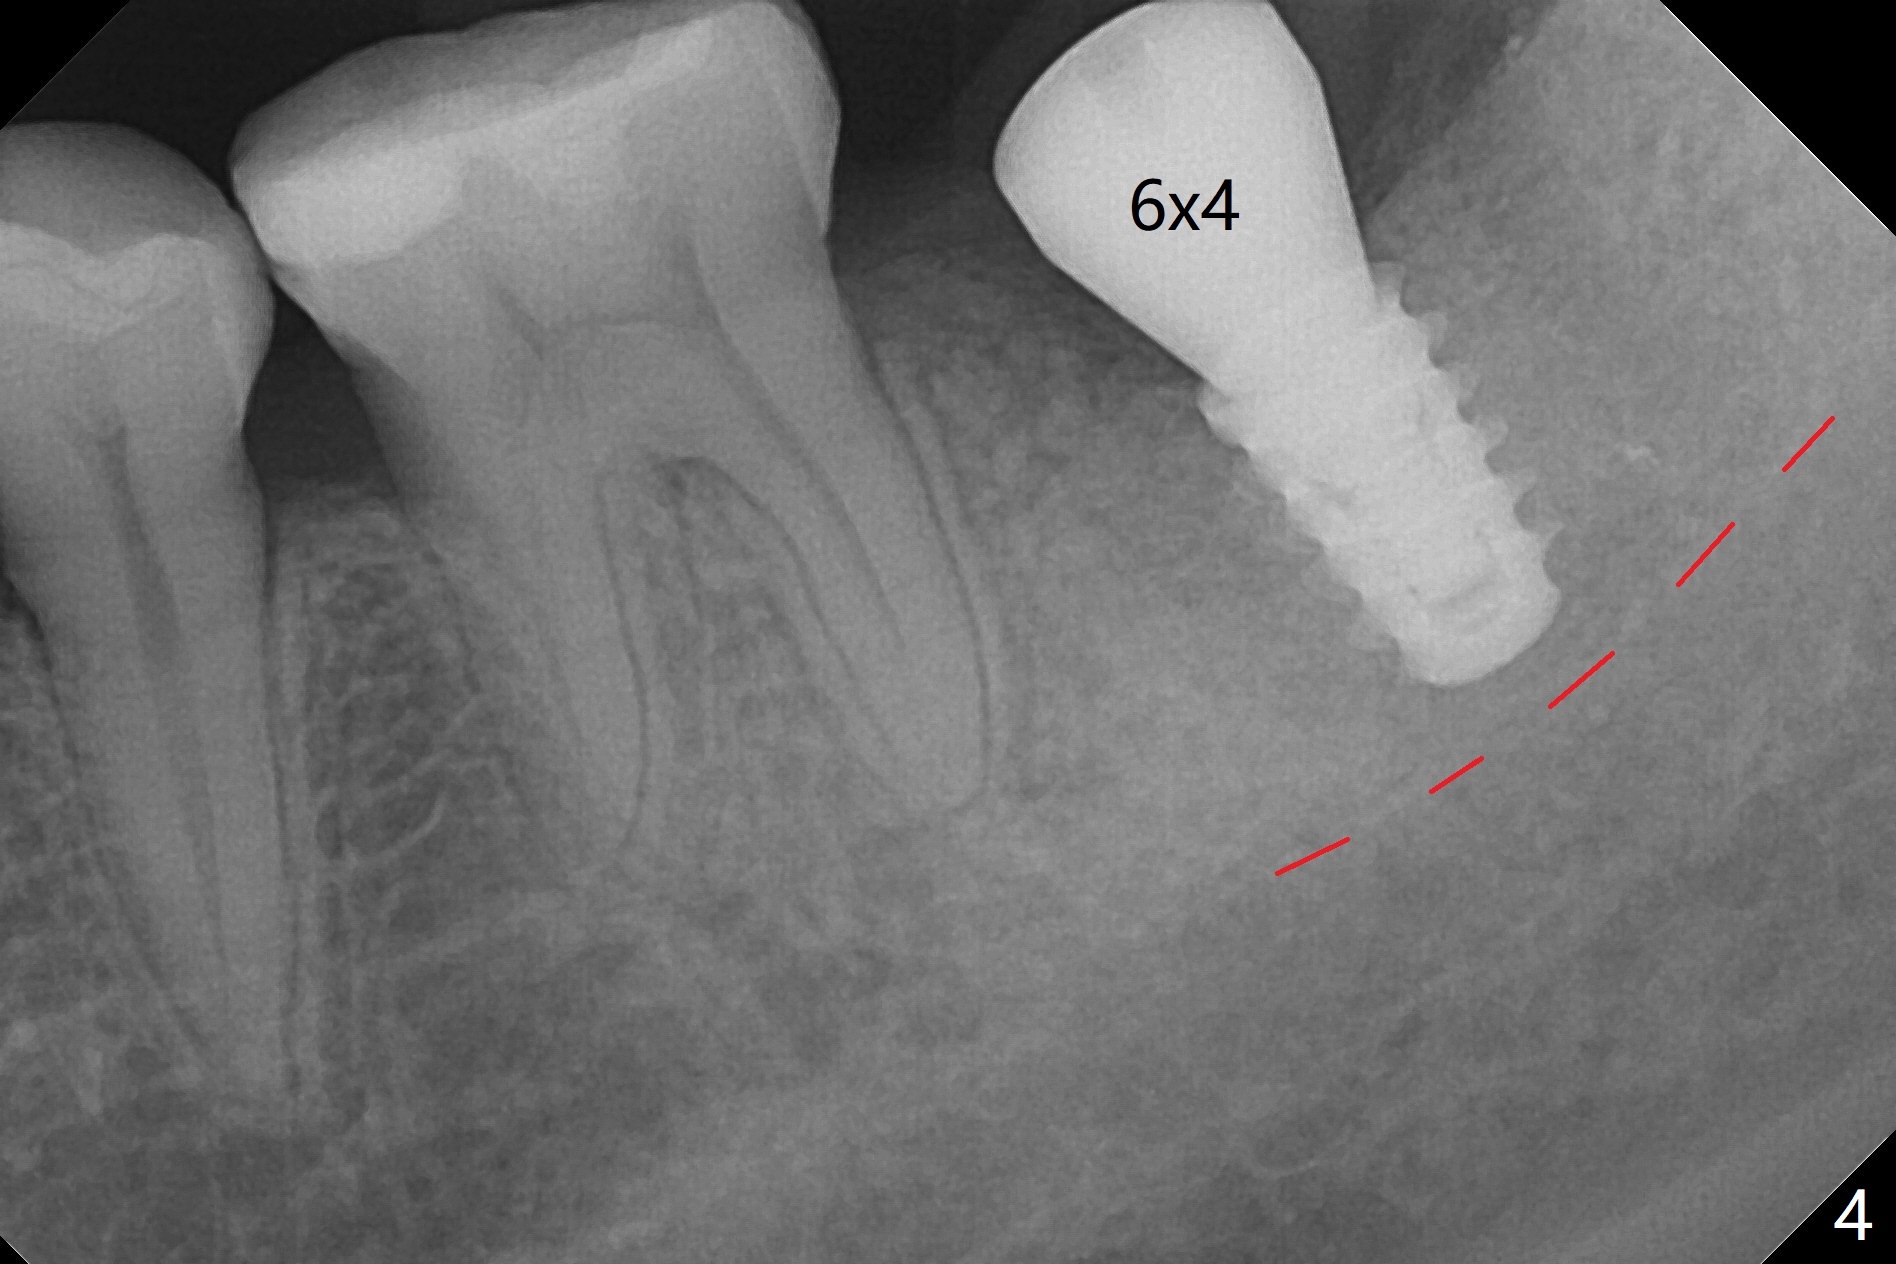

Six months post socket preservation at #18 (with moderate atrophy, Fig.1), a simplified surgical guide (Fig.2 with metal sleeve of 5 mm height and 2.93 mm diameter) determines initial osteotomy with 3.3 mm Magic Drill (MD), followed by 4.8 mm MD for 9 mm (gingival level) free hand. Since a 5x7 mm IBS implant is placed incompletely and in low stability (Fig.3 (in the graft bone)), a 4.3 mm MD is used for ~1 mm deeper. The implant is reseated to more satisfactory level (Fig.4: ~ 1 mm from the upper border of the Inferior Alveolar Canal (red dashed line)). The fearful patient is extremely pleased with quickness of the procedure as compared to that at #30 free hand. The wound heals normally 2 weeks postop. When she finishes the follow up appointment, she voluntarily talks to another patient who is hesitant about implant treatment. Impression is taken 5 months postop (Fig.5,6). There is no gap between the crown and abutment using abutcoping technique (Fig.7,8). The crown at #18 looks low probably related to long termed edentulism (Fig.9). The access hole is lingual (Fig.9), because the implant was placed lingual (Fig.10) due to use of a partial guide (Fig.11).